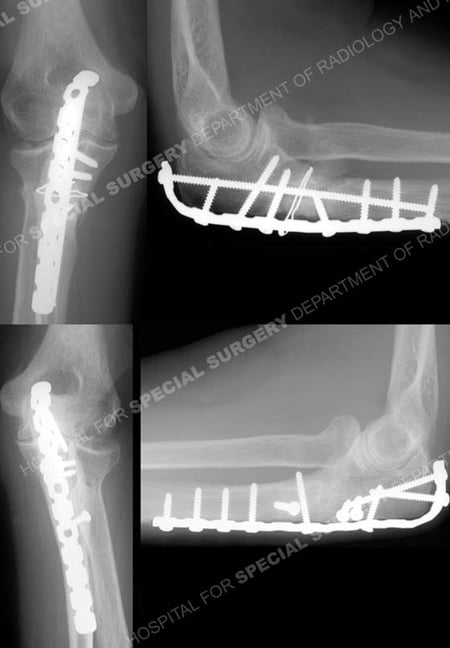

Anteroposterior and lateral radiographs at 12 months illustrating healed Monteggia

fracture-dislocations in excellent alignment.